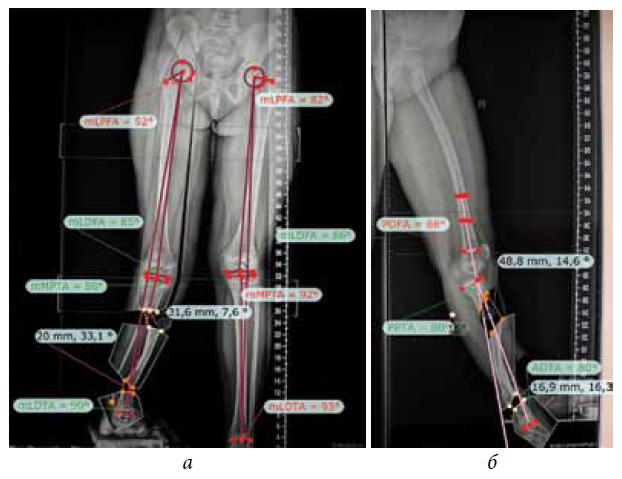

The second stage of treatment was the recommended correction of the resulting multiplane deformities of the affected lower extremity (mMPTA was 94°, mLDTA was 71°, aPPTA was 90°, and aADTA was 59°, shortening the affected lower limb by 8.0 cm). For lengthening and deformity correction of the right lower limb, the patient underwent preoperative planning for deformity correction with the exception of osteotomies in the area of consolidated pseudoarthrosis at the age of 9 years. According to the plan, a two-level osteotomy of the shin bones was performed, as along with lengthening by 5 cm by the Ilizarov method. The deformity was corrected using a repositional unit with Ortho-SUV computer navigation properties. The period of deformity correction was 58 days, and the external fixation period was 247 days. At the end of the fixation period, a recurrence of deformities of the tibial bones was detected with the formation of a deformity apex at the level of the proximal and distal tibial growth zones (mMPTA was 94°, mLDTA was 82°, aPPTA was 86°, and aADTA was 80°) (Fig. 1–4). We applied hemiepiphysiodesis to correct the recurrence of valgus deformity of the tibia. The period of deformity correction was 269 days. The reference angles values of the tibia were within the accepted ranges.

Fig. 3. Preoperative planning for deformity correction in a patient with cCPASB using specialized software: а — anterior-posterior view; b — lateral view

Fig. 4. Roentgenograms of the patient with cCPASB following deformity correction of the bones of the right tibia: а — anterior-posterior view; b — lateral view